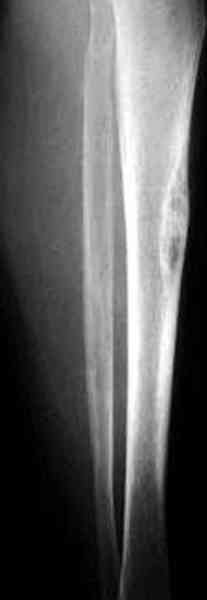

Недавно на нашей ежемесячной Morbidity&Mortality conference мы

разбирали похожий случай, ложный сустав большеберцовой кости после

резекции опухоли.

Имя     : 2 adamantioma lat preop.jpg